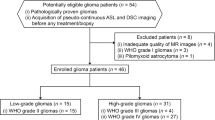

Thirty-nine patients with clinical and radiological suspected low-grade glioma, referred to the neurosurgical department between May 2010 and November 2012, were prospectively and consecutively recruited [19]. The institutional review board approved the study protocol, and all patient participation was based on written informed consent. An intracerebral tumour-suspected lesion on morphological MRI with high signal intensity on T2 fluid attenuated inversion recovery (FLAIR) and with no or minimal contrast enhancement was regarded as a suspected low-grade glioma (assessed by a neuroradiologist with 30 years of experience). Exclusion criteria for the present study were other histological diagnosis than grade II or grade III glioma (n = 4), no histologically diagnosis available (n = 8) or obtained more than 12 months after the study MRI (n = 2). Thus, 25 patients with grade II or grade III glioma were enrolled in the present study. The clinical characteristics of these 25 patients are shown in Table 1. The study MRI was performed pre-operatively in all but one patient. This patient (patient 2) had a biopsy performed 6 months prior to the study MRI.

Histological tumour diagnosis was obtained by neuronavigation-guided needle biopsy (n = 4), open biopsy (n = 3) or resection (n = 18), as previously described [19]. Estimation of extent of resection was based on 48 h post-operatively MRI except in one case who had a post-operative CT and is presented in Table 1.